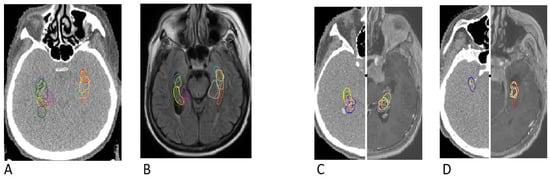

3.2. Overlapping Contours